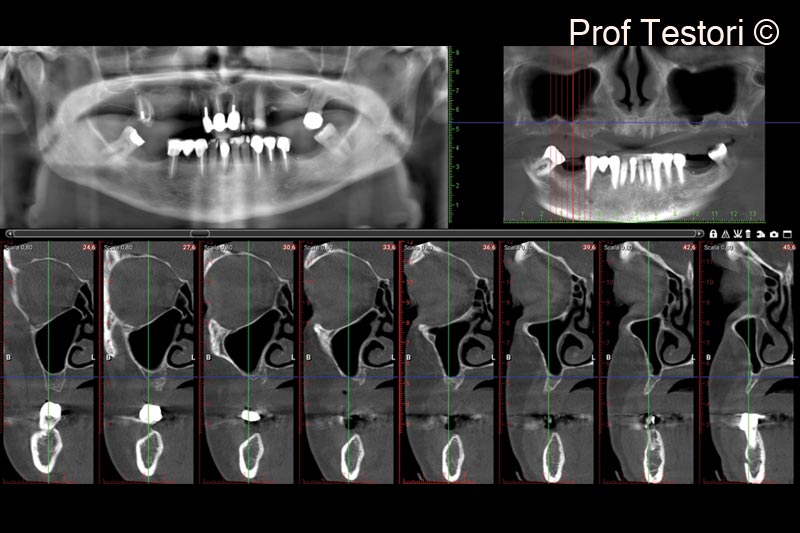

11. Immediate post-op panorex after healing and CBCT

12. 6-months follow-up CBCT performed before implant placement